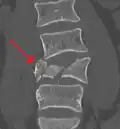

Diagnosis is by medical imaging.

A burst fracture of L4 as seen on CT -